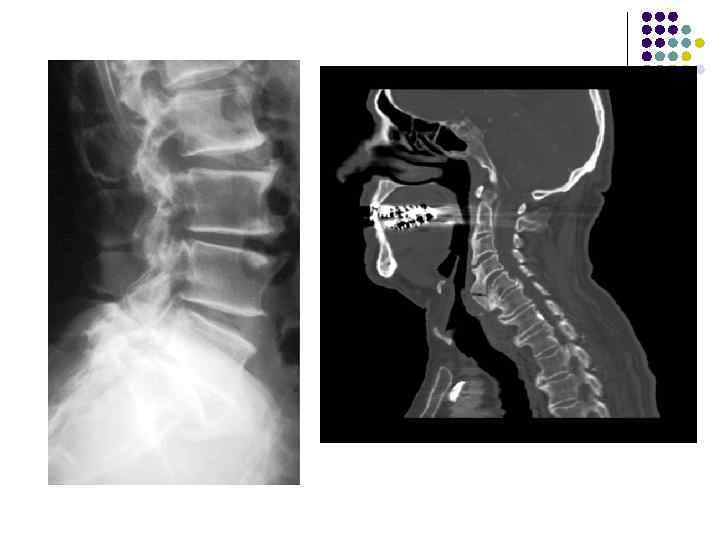

Лигаментозобызвествление и оссификация передней продольной связки